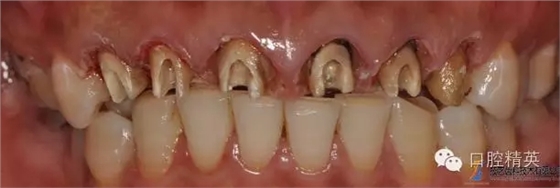

主訴:重新修復(fù)上前牙?,F(xiàn)病史:患者上前牙8年前曾在外院烤瓷冠修復(fù)牙齦腫脹近日加劇來我院就診。